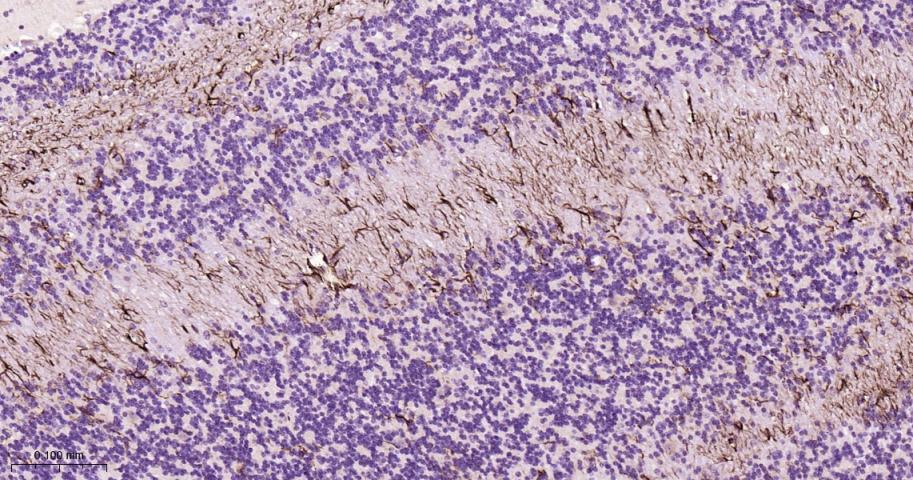

GFAP (Glial fibrillary acidic protein) is a member of the class III intermediate filament protein family. GFAP is heavily and specifically expressed in astrocytes and certain astroglia of the central nervous system, in satellite cells of peripheral ganglia, and in non-myelinating Schwann cells of peripheral nerves. In addition, neural stem cells strongly express GFAP. Antibodies to GFAP are very useful as markers of astrocytic cells. In addition, many types of brain tumor, presumably derived from astrocytic cells, heavily express GFAP. GFAP is also found in the lens epithelium, Kupffer cells of the liver, in some cells in salivary tumors and has been reported in erythrocytes. GFAP is used as a marker to distinguish astrocytes from other glial cells during development. Mutations in this gene cause Alexander disease, a rare disorder of astrocytes in the central nervous system. Alternative splicing of the GFAP gene results in multiple transcript variants encoding distinct isoforms.

*5. 发表论文时引用本产品的写作建议 "IHC0101R, Bioss Antibodies"。引用示例: “Rat tissue sections using Rat GFAP IHC Kit (IHC0101R, Bioss Antibodies) were stained for GFAP according to the manufacturer's instructions.”